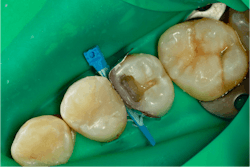

Once this step is done, the separating ring is no longer of any use, so I remove it to clear my path to place and shape the final increment (figure 11).

The last increment of Tetric PowerFill is placed, shaped, and cured. Once this is finished, the matrix and wedge are removed.

As you can see, we do have some flash to finish off. We will always have flash with resin composite restorations. The key is to get the flash in a manageable position on the tooth. As can be seen below, the flash is on the midbuccal and midpalatal; easy to finish with either a finishing bur or a disc. We don’t want to generate flash in between the teeth where it is difficult to finish. The Garrison 3D Fusion system does a tremendous job of this (figure 12).